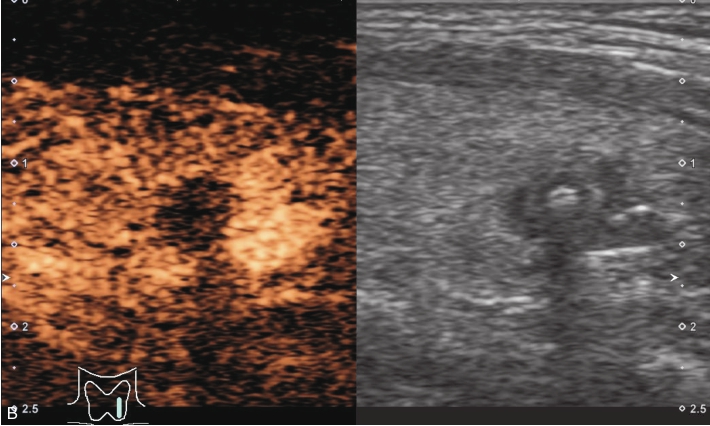

女性,67岁,体检发现甲状腺右叶结节1年。体格检查:颈软,气管居中,无压痛,双侧甲状腺未触及明显肿块。实验室检查:A-TP 10.00IU/ml,A-Tg 45.40IU/ml,TSH 3.26mIU/L,FT3 5.13pmol/L,FT4 15.35pmol/L。

甲状腺右叶下极可见一低回声结节,紧贴甲状腺包膜,突出于甲状腺包膜,大小约0.82cm×0.72cm×0.55cm,呈椭圆形,边界清楚,内部为低回声,分布不均匀,后方回声稍增强,CDFI显示结节内未见明显血流信号,弹性成像示弹性评分为3分,见图1-3-11。

图1-3-11 甲状腺“木乃伊”结节

A、B、C、D.甲状腺“木乃伊”结节常规超声图像

经肘正中静脉团状注射造影剂SonoVue1.2ml后,13s周围甲状腺组织开始增强,病灶边缘部呈稍增强,病灶内部始终呈无增强,在整个造影过程中病灶内始终呈无增强,见图1-3-12、ER1-3-6。

“木乃伊”结节超声造影表现为无增强。

部分良性甲状腺结节囊液吸收后超声表现为低回声、缩小,超声表现为可疑恶性征像,二维超声表现与甲状腺乳头状癌难以鉴别,超声造影可以明确病灶内有无增强,提高诊断准确性。

图1-3-12 甲状腺“木乃伊”结节造影图像

A.造影示低回声结节呈无增强;B.增强晚期仍呈无增强